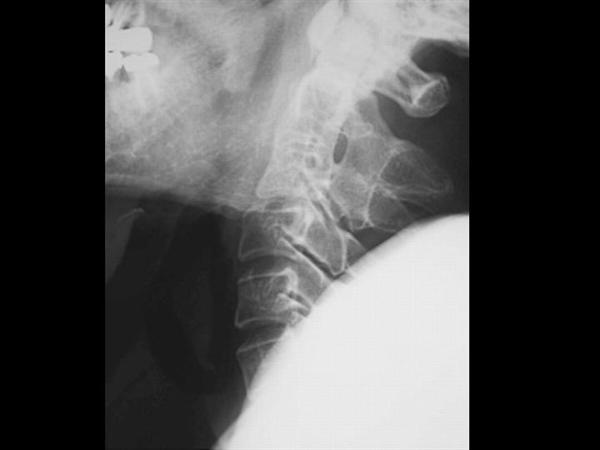

9. A 67-year-old man falls forward from standing height sustaining a hyperextension injury to his neck. He has neurological deficits present on physical examination. A radiograph, CT scan and MRI are seen in Figures A, B and C. Which of the following MOST likely characterizes his neurologic examination?"

FIGURES: A

B

C

DISCUSSION: The patient in the scenario has a central cord syndrome. The images show a relatively kyphotic spine with moderate osteophyte formation from C4 through C6. The MRI shows stenosis without cord signal change. Central cord syndrome is characterized by motor deficits more pronounced in the upper extremities than lower extremities. In addition, finger and wrist motor function is more affected than shoulder and biceps function. Sensory deficits are usually minimal.

Nowak et al reviewed central cord syndrome. It is the most common incomplete spinal cord injury, typically resulting from an extension injury. It presents as a spectrum from hand weakness to quadraparesis with sacral sparring. Early surgical treatment is still controversial.